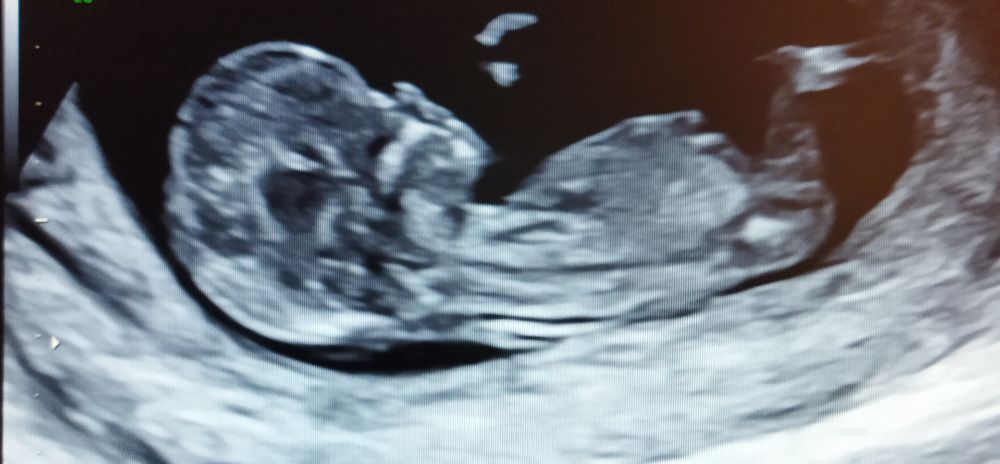

Вот для примера мой мальчик) я вижу тут бугорок к верху, а у вас мне кажется девочка. Изображение

Изображение Вот «моя девочка» на 1 скрининге пару недель назад )Я если честно не понимаю в этом ,но Пятых на 99,9% уверена ,что девочка )

Однозначно, я тоже видела что у девочек не просто параллельно, а прямо внизу опущен бугорок